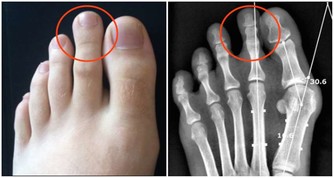

膝關節壽命只有60年

一方面我們需要鍛煉大腿和臀部的肌肉群。但是另一方面,我們又不能以傷害膝關節為代價,因為膝關節的壽命由基因決定,是60年,過度使用會加重對它的磨損,並且不可修復。

在爬山和爬樓梯的時候,膝關節會承受超過本身體重3到4倍的壓力。尤其是50歲以後,人的膝關節多少都會有些磨損的情況,此時,就要減少此類運動。對於有些有過膝關節損傷的朋友40歲以後就要特別注意了。